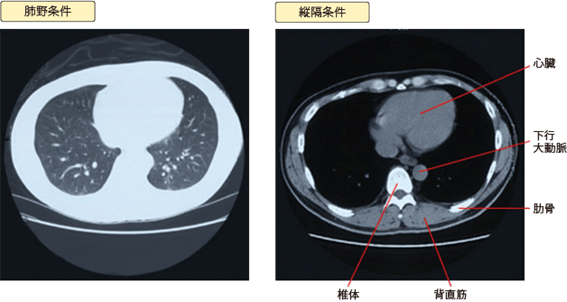

CT画像を見ていただくと黒い部分と白い部分があることに気づかれると思います。白いほうを肺野条件、黒いほうを縦隔条件といいます。ほとんどの場合、同じデーターを2種類の出力で見せているのです。

このときに見たいものをある程度強調しないと見落としが発生します。そこで、肺の中の細い血管、気管支、肺胞(肺を構成している小さな袋です)などを強調し白く見えるのが肺野条件です。

一方、心臓、大動脈、リンパ節、食道、脊椎骨などが集中している縦隔の状況を確認するために出力し、黒っぽく見えるのが縦隔条件です。